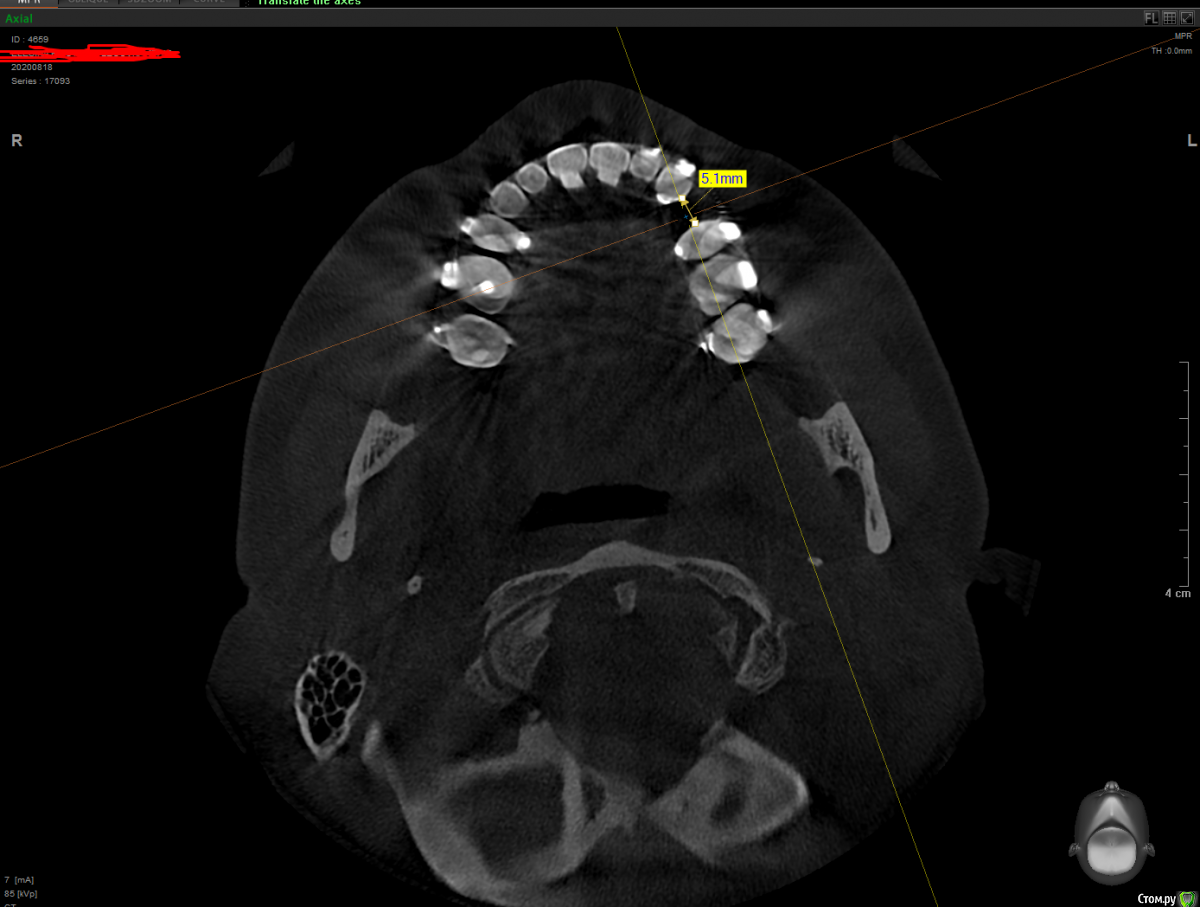

It'sGeorgy Опубликовано 19 ноября, 2020 Поделиться Опубликовано 19 ноября, 2020 Здравствуйте.Вот такая ситуация:Ставить планирую по шаблону с направляющей фрезой из Пикассо. Дополнительно ССТ с неба. Не могу определиться с имплантатом:Straumann BLT 2.9x10 или Straumann BL 3.3x10Производитель не рекомендует 2.9 на премоляры, но тут и размер коронки меньше, чем у стандартного премоляра. С другой стороны, жевательным зубом он быть от этого не перестает.Что посоветуете? Ссылка на комментарий

It'sGeorgy Опубликовано 19 ноября, 2020 Автор Поделиться Опубликовано 19 ноября, 2020 Ширина кости, в первую очередь. После установки диаметра 3.3мм останется по 1.3мм вестибулярно и орально. На мой взгляд, это очень близко к минимальной допустимой ширине стенок. Собственно, из этого и появились сомнения: может пожертвовать 0.4 титана, поставив диаметр 2.9, и получить лишние 0.4 кости. Опять же, небольшой размер коронки на это так же подталкивает. Вы бы поставили 3.3? Ссылка на комментарий

red_butler Опубликовано 20 ноября, 2020 Поделиться Опубликовано 20 ноября, 2020 Мне кажется здесь рано имплантировать, мезиодистальное настояние мало, пусть ортодонт продолжит работу. А по кости конечно 3,3 2 Ссылка на комментарий

Nazim_NV86 Опубликовано 22 ноября, 2020 Поделиться Опубликовано 22 ноября, 2020 (изменено) Здравствуйте.Вот такая ситуация:1.png2.png3.pngСтавить планирую по шаблону с направляющей фрезой из Пикассо. Дополнительно ССТ с неба. Не могу определиться с имплантатом:Straumann BLT 2.9x10 или Straumann BL 3.3x10Производитель не рекомендует 2.9 на премоляры, но тут и размер коронки меньше, чем у стандартного премоляра. С другой стороны, жевательным зубом он быть от этого не перестает.Что посоветуете?Смотрите не на толщину кости, а на свои возможности. Если бы апроксимально место позволяло, я бы и 4.1 пристроил. Если под рукой есть диск или пьезо + экспандеры, то сделать +1-1.5мм вестибулярно вообще не проблема на ВЧ. Изменено 22 ноября, 2020 пользователем Nazim_NV86 1 Ссылка на комментарий